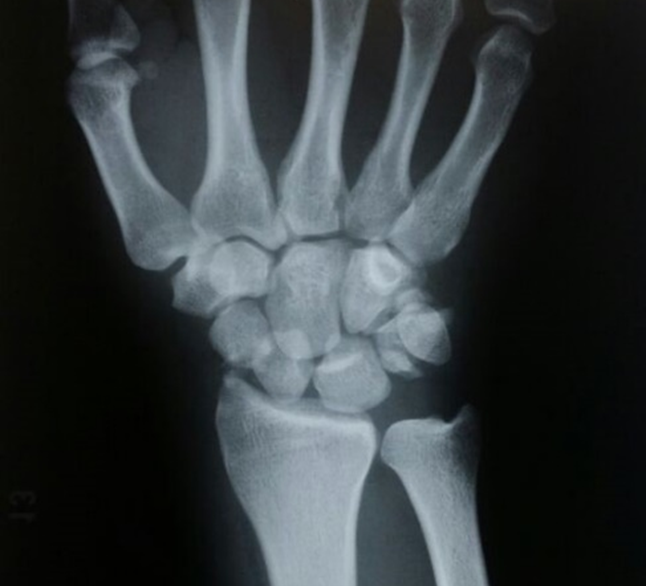

Plain X-rays, asking for scaphoid views and should include a posteroanterior (PA) and lateral of the wrist, ulnar deviation PA and supination oblique views. A CT scan is suitable for fracture morphology, but should only be requested by the treating surgeon. MRI is the most sensitive investigation for picking up occult scaphoid fractures. If a scaphoid fracture is suspected clinically, but the X-ray does not show a fracture, then the patient must be placed in a backslab and seen again after 10-14 days for a repeat examination and X-ray. If earlier confirmation is required, then an MRI scan should be performed.